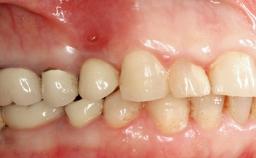

Peri-implantitis Modified by Submucosal Excess of Cement: Regenerative Peri-implantitis Therapy and Six-year Follow-up

A 30-year-old female patient was referred to the Department of Periodontology of the University of Bern, Switzerland, by a dentist in private practice. Tooth 45 had been congenitally missing and had been replaced with a titanium implant three years prior to the first visit at the Department of Periodontology. The tissue level implant had a diameter of 4.1 mm, a length of 12 mm, and a sandblasted and acid-etched (SLA) surface (Straumann® Dental Implant System; Institut Straumann AG, Basel, Switzerland). The metal-ceramic crown on implant 45 had been cemented permanently. Implant 45 had been diagnosed with peri-implantitis by the referring dentist in the course of regular supportive care.